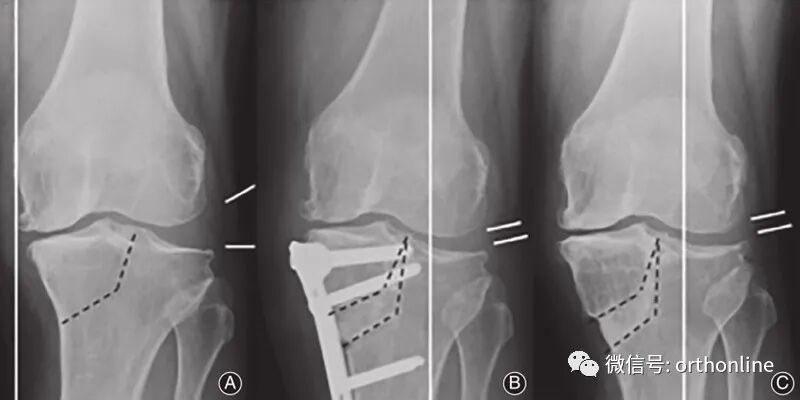

图1 胫骨高位截骨术(HTO)

图3

传统的HTO技术无法对关节内畸形进行矫正,因此在合并外侧半脱位的重度膝关节骨关节炎病例中往往难以达到满意的治疗效果。Chiba[9]基于传统HTO技术所面临的困境,于1992年提出了胫骨髁外翻截骨术(tibial condylar valgus osteotomy, TCVO)。TCVO为开放性楔形HTO的一种,由胫骨近端内侧向髁间隆起行"L"形截骨,旨在矫正膝内翻、外移下肢力线的同时修复半脱位的外侧膝关节。日本学者Teramoto T[10]等认为TCVO适用于所有年龄、所有等级的膝内翻OA患者。TCVO的基本原则是通过关节内畸形的关节内矫正来稳定膝关节。这种关节内截骨术改善了骨性和软组织的不稳定性,不需要单独的韧带重建。临床结果证实经tvo治疗后,患者疼痛得到改善,能够恢复繁重的体力劳动和运动活动。国内学者王峰、康庆林团队[11]对接受TCVO手术的内翻型单间室膝关节骨关节炎患者32例(45膝)进行回顾性分析,发现TCVO治疗膝关节外侧间隙增宽、关节线会聚角增大的内翻型单间室膝关节骨关节炎可以取得良好的早期疗效,有效矫正膝关节内翻畸形并外移下肢机械力线,缓解术后早期膝关节疼痛及改善日常活动能力。